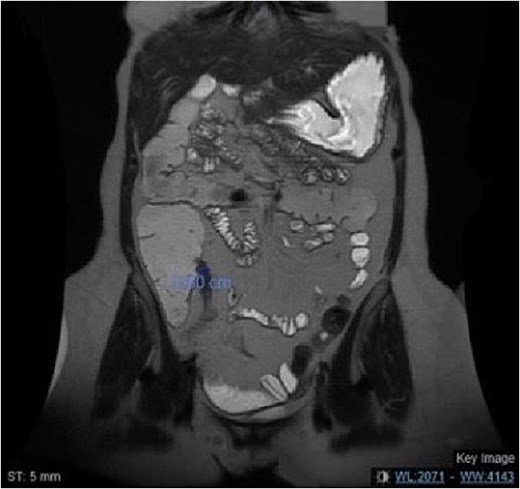

Computed tomography (CT) scans revealed progressive terminal ileal stricture with small bowel dilation and sinus tracts. Colonoscopy showed narrowing and active ileitis, leading to Budesonide treatment. Despite steroid tapering and azathioprine initiation, she had a severe flare-up with obstipation and distension. Magnetic resonance enterography (MRE) (Fig. 1) confirmed fibrosis, and she failed medical therapy after eight doses of vedolizumab.

MRE of the abdomen showing a coronal view of the short segment fibrosis at the terminal ileum with mild dilated small bowel loops.